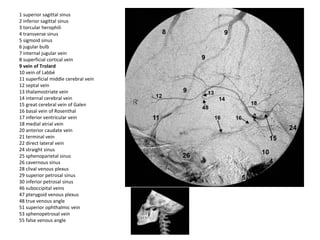

1 superior sagittal sinus

2 inferior sagittal sinus

3 torcular herophili

4 transverse sinus

5 sigmoid sinus

6 jugular bulb

7 internal jugular vein

8 superficial cortical vein

9 vein of Trolard

10 vein of Labbé

11 superficial middle cerebral vein

12 septal vein

13 thalamostriate vein

14 internal cerebral vein

15 great cerebral vein of Galen

16 basal vein of Rosenthal

17 inferior ventricular vein

18 medial atrial vein

20 anterior caudate vein

21 terminal vein

22 direct lateral vein

24 straight sinus

25 sphenoparietal sinus

26 cavernous sinus

28 clival venous plexus

29 superior petrosal sinus

30 inferior petrosal sinus

46 suboccipital veins

47 pterygoid venous plexus

48 true venous angle

51 superior ophthalmic vein

53 sphenopetrosal vein

55 false venous angle